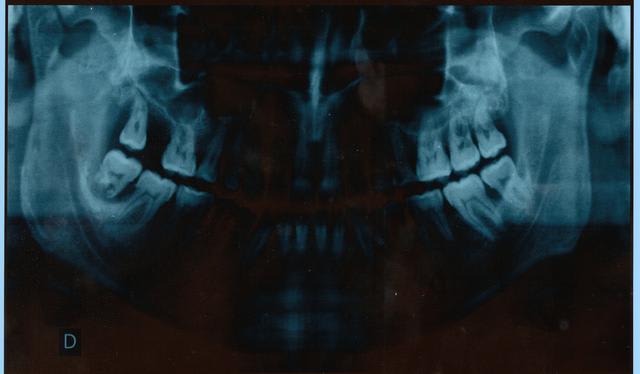

un gars de 40 ans bien portant vient consulter pour des douleur au froid au secteur gauche et une mobilité de la 48

apres examen et tout le barratin, la radio s'impose pour la 48

boh je vous cache pas, les retroalveolaires m'ont revelé une lyse osseuse avec une rhysalyse aussi, alors j'ai demandé la pano, pour plus d'info.

qu'en diriez vous???kyste??? dentigère ou quoi???

C'est quoi la dent qui se balade sous la 47 ?? est-ce bien une dent d'ailleurs ?? elle est pas trop terrible la photo de la pano ;-))

quelqun voit quelque chose sous la 47????

Sous la 47, tu vois bien une image ou c'est juste un artéfact ??

IL faut bien cureter toute la lésion apicale et l'envoyer en anapath.

cette lésion est suspecte

ce n'est pas une lésion habituelle de type kyste, l'anapath est obligatoire.

en fait la rhysalyse est un signe que la lesion est ancienne avec une evolution lente, mais il reste à savoir sa nature

Pour la 47 je sais pas mais l'image fournie, même si elle est médiocre, me suffit pour dire qu'il y a une lésion suspecte dans la région apicale de la 48 avec une rhyzalyse.